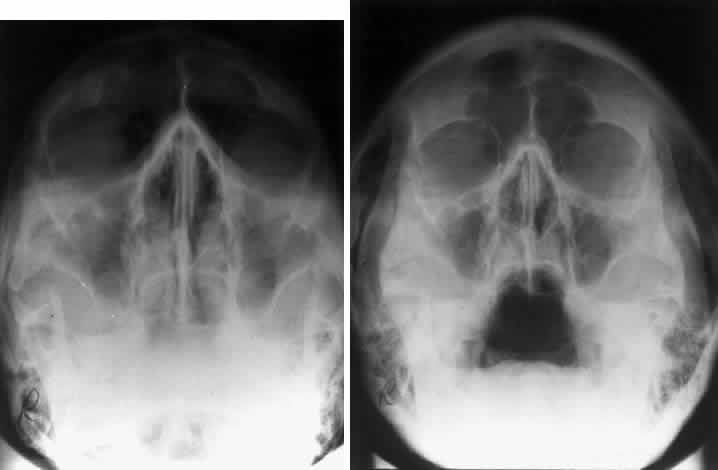

Bony destruction usually results from a rapidly growing process such as a tumor of the lacrimal gland or paranasal sinuses (Fig. 12). Sinusitis or a mucocele can also cause bone destruction or dehiscence of the orbital bones. Mucoceles most often originate in the frontal and ethmoid sinuses, and destruction of bone is noted radiographically in 70% of cases24 (Fig. 13). Encephaloceles may also cause a disruption in the orbital bones, usually superomedially. Neurofibromatosis is associated with dysplasia that can involve large segments of the greater wing of the sphenoid. Pulsating exophthalmos may be a clinical finding.

Fig. 13. Frontal sinus mucocele extending into the right orbit. The orbital extension was responsible for downward displacement of the globe in this patient. The frontal sinus is the most frequent origin for mucoceles.

The orbital dimensions—orbital margin, superior orbital fissure, optic foramen—should be symmetric in size and shape. Mild asymmetry may be normal, but marked asymmetry should alert the clinician to search for pathologic causes. The vertical dimension of the orbit is best measured in the frontal plane with a nose-chin view as described by Lloyd.25 A difference of 2 mm or more is considered abnormal. The orbital dimensions can increase with any long-standing mass lesion that raises the intraorbital pressure. Lesions outside the muscle cone are more likely to cause localized enlargement, whereas intraconal lesions lead to a generalized orbital expansion. Such lesions include hemangiomas, optic nerve gliomas, meningiomas, and congenital glaucoma with buphthalmos or microphthalmos with cyst. Smaller orbits may be due to microphthalmos, enucleation in childhood, or congenital facial disorders.

The superior orbital fissure has interpersonal and intrapersonal variations. The fissure should be symmetric, but there is no good measurement that identifies pathology, other than marked asymmetry. The fissure can be enlarged by infraclinoid aneurysm, carotid-cavernous fistulas, pituitary tumors, and meningiomas.26 Less common causes for enlargement include hemangiomas, lymphoma, mucocele of the sphenoid sinus, and neurofibromatosis (Fig. 15).

Fig. 15. Enlargement of the left superior orbital fissure (arrow) by neurofibromatosis. The Caldwell projection gives the best view of this fissure.